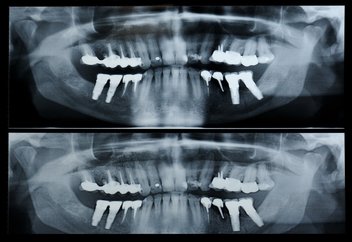

A panorex is a very impressive piece of imaging machinery in that it is capable of identifying many issues and structures that a normal x-ray is not. Initially you will stand with your chin on a small ledge. Once positioned in the machine, it will rotate around your entire head taking a full 360 degree view of the teeth, head, sinuses and bones.

The ability to view the full structure of your head as a whole is very informative to the dentist. It will allow us to see any potential problems and make sure that everything is functioning as it should be. The panorex is capable of viewing specific types of structural problems, infections or asymmetry among many others.